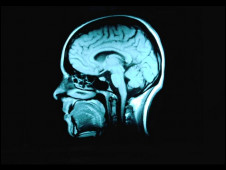

現在,英國和芬蘭的研究人員針對三個大型的有關老年化的研究進行分析,這三個大型研究一共觀察了872名已經去世的老年人的大腦。

研究人員發現,在他們去世之后,他們大腦里出現失智癥的病變,與他們接受的教育程度沒有明顯關系。

但是接受教育程度越高的人,就越能適應老年之后帶來的種種問題,包括記憶力減退。